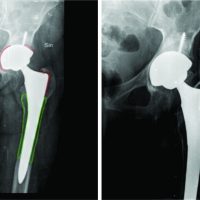

A 21-year-old male patient was involved in a traffic accident in April 2017, resulting in a Grade IIIB (Gustilo-Anderson Classification) exposed fracture of the left lower limb with soft tissue involvement and loss of the lateral compartment of the knee with a massive osteochondral defect. Initially, he was treated in another institution with a transarticular external fixator in extension, and the soft tissue defect was covered with a latissimus dorsi free flap and skin grafts in the leg. He developed graft necrosis, requiring multiple debridements. The defect was covered with an anterolateral right thigh-free flap and the edges with split-thickness skin grafts. At that moment, the patient refused a knee arthrodesis. Three months after the traumatic event, the patient was referred to our institution with moderate pain and purulent discharge from the proximal Schanz screws (Fig. 1). A two-stage surgical treatment approach was planned, including stage 1: eradication of infection and recovery of joint function and stage 2: transplantation with bipolar FOCA. Stage 1 started with the removal of the transarticular external fixator and debridement with femur and tibia sequestrectomy. Cultures were taken, and knee mobilization was performed; the defect was filled with polymethylmethacrylate beads (PMMA) mixed with gentamicin plus vancomycin. Oxacillin-sensitive Staphylococcus aureus was isolated, and intravenous cefazolin was indicated for 6 weeks. A computerized axial tomography (CAT) scan with 3D mirror reconstruction of both knees was requested for surgical planning to make the cutting guides and cats of the femoral condyle and the external tibial plateau (Fig. 2). The measurements of the defect in the tibia were anteroposterior 6 cm, transverse 8 cm, length 8 cm, and in the femoral condyle: anteroposterior: 7.3 cm, transverse 8.5 cm, and length 6 cm. Eight days after the first surgery, the second stage 1 procedure was performed to improve joint mobility. In this surgery, the reconstruction of the lateral compartment was performed with PMMA bone cement spacers, which were designed based on the 3D anatomical models (Fig. 2d). Functional recovery was achieved with a Judet’s quadricepsplasty, achieving a knee range of motion (ROM) of 0–90° (Fig. 3). Post-operatively, continuous passive mobilization machine therapy was initiated for 5 days, and physical therapy focused on improving ROM and pain with proprioception and quadriceps strengthening exercises; the patient also received education for walking with crutches. Cultures taken during this second surgery were negative, and cefazolin was continued until the treatment was completed. Once stage 1 was completed, the process of searching for a fresh allograft compatible in size with the patient’s tomographic measurements began. Due to delays in the approval of the FOCA transplantation by the health insurance company, stage 2 was initiated 15 months after the accident (or 12 months after the last surgery). At that time, radiographic follow-up showed preserved joint relationships and decreased femorotibial joint space with the osteosynthesis material in situ, with no sign of reactivation of the infection (Fig. 4). Once the allograft was obtained, X-rays and CAT scans of the allograft were taken to 3D-print the cutting guides and obtain an anatomical coupling between the defect and the fresh allograft. Before starting reconstructive surgery with FOCA, the 3D models were sterilized and sealed. Digital planning and cutting guides were performed according to the 3D reconstruction in Fig. 2. The cement spacers in the femur and tibia, as well as all the osteosynthesis material, were removed, and with the help of cutting guides, the defect was regularized to maximize the articular congruence of the femoral condyle and the external tibial plate. Bone tunnels were made in the femur, tibia, and fibula for anatomical ligament reconstruction. The allograft was fixed with interferential screws and plates in the distal femur and proximal tibia under fluoroscopic visualization. Reconstruction of the posterolateral corner, including the lateral collateral ligament, the popliteofibular ligament, and the popliteus tendon, was performed using the technique described by Chang et al., [7] achieving adequate joint stability. As shown in Fig. 5 and 3D printing, surgical guides allowed an anatomical and congruent joint reconstruction of the articular surface. Since the first post-operative day, the rehabilitation process has begun with isometric quadriceps exercises, active/active-assisted ROM exercises, and gait training with partial load. On the 5th post-operative day, the patient left the institution with adequate pain control and a ROM of 0–40°. Post-operative radiographs showed recovery of joint congruency, alignment, and adequate fixation of the bipolar FOCA (Fig. 6). During follow-up, no complications were reported, and there were no signs of infection reactivation. At the last follow-up, 5 years after transplantation with FOCA, the patient reported no functional limitations (mobility, self-care, usual activities) or pain but reported moderate symptoms of anxiety or depression through the EQ-5D-3L questionnaire. Nevertheless, he rated his overall health status with a score of 90 on a scale of 0–100. The final ROM of the left knee was 0–90°, without functional instability. Fig. 7 shows the radiological follow-up at the last control. The patient provided consent for publication.